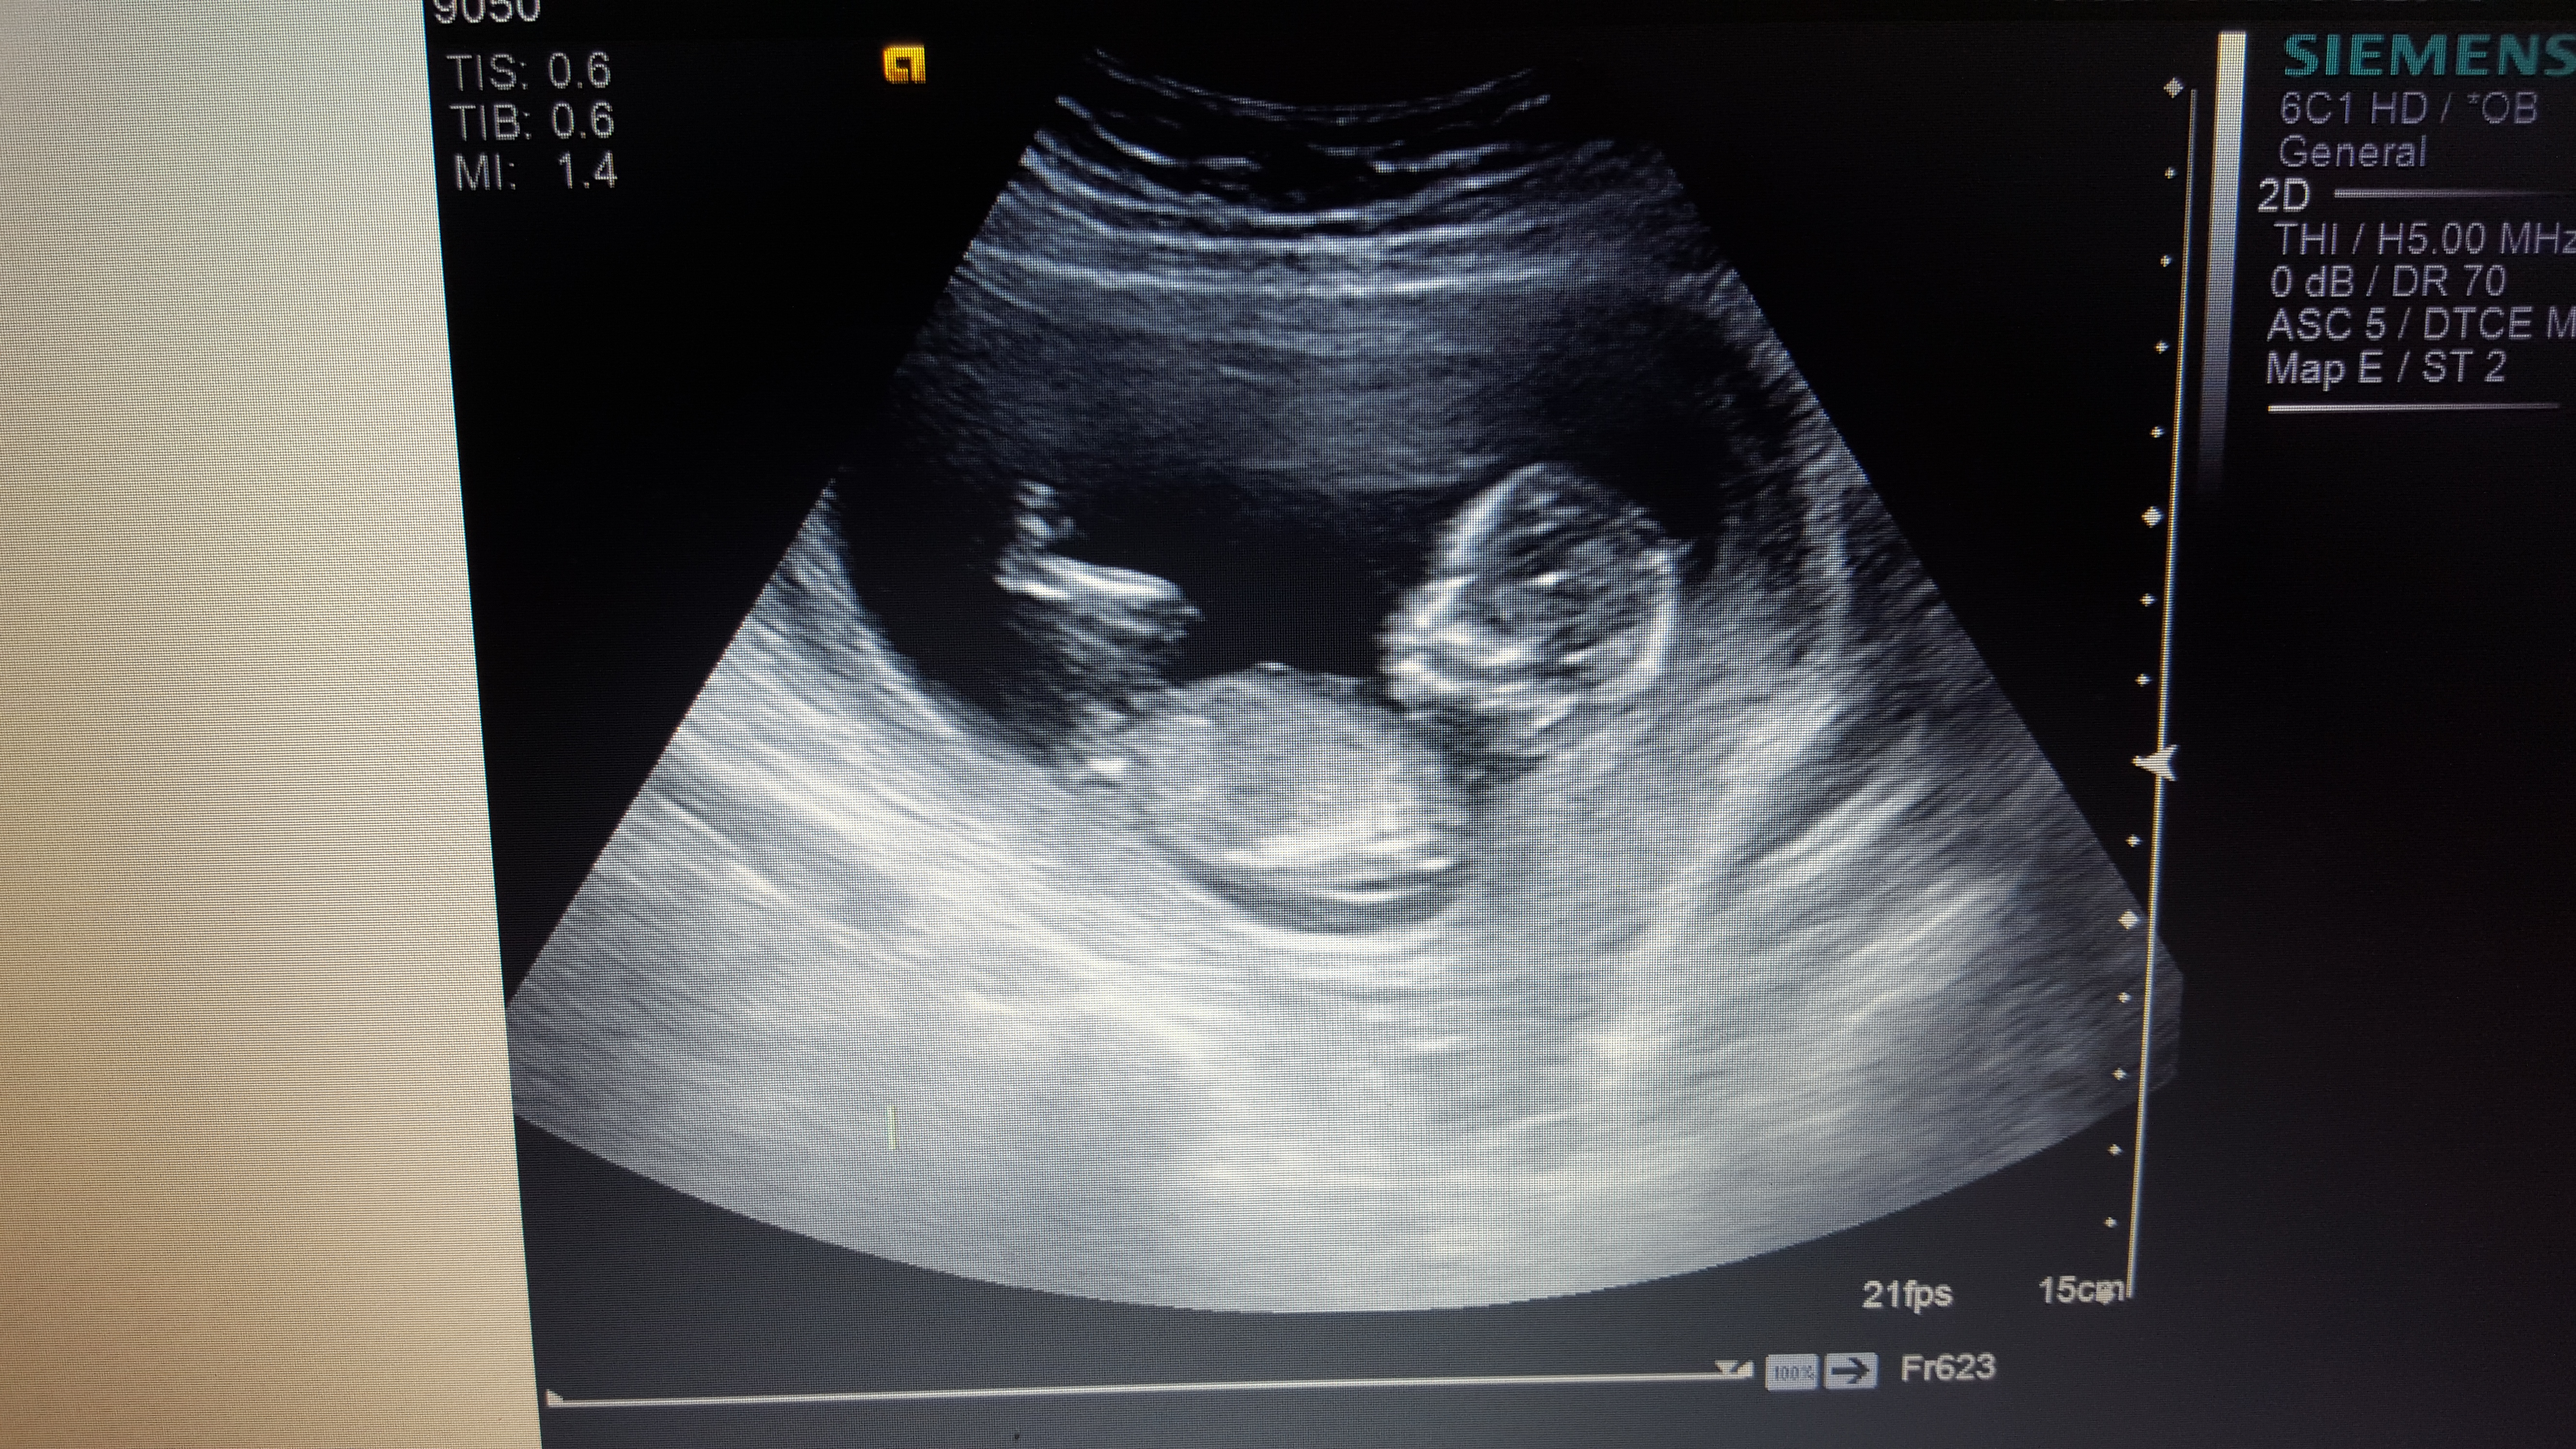

Boy or girl?

How far along?